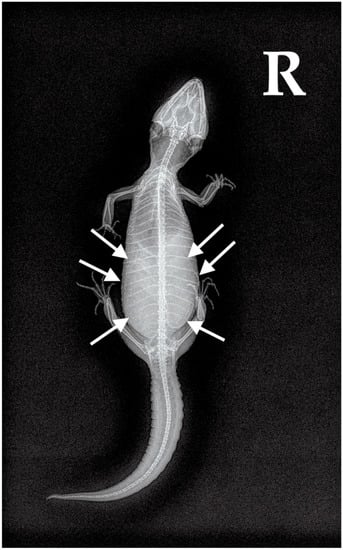

2.2.1. Case 1